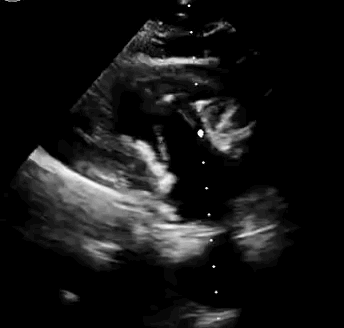

本次臨床前研究經(jīng)右側(cè)頸靜脈置入LuX-Valve Plus輸送系統(tǒng)可調(diào)彎鞘管,在DSA及超聲引導下將人工三尖瓣瓣膜植入到原有三尖瓣位置,利用獨特的錨定技術(shù)將人工瓣膜支架可靠固定在預(yù)定的位置。

上海中山醫(yī)院葛均波院士、錢菊英院長、周達新教授、潘文志教授、潘翠珍教授、李偉教授共同完成此次臨床前研究。術(shù)后葛均波院士對Lux-Valve Plus的器械操作性能給予了高度評價,DSA和超聲影像也顯示出在本次研究中Lux-Valve Plus的安全性和有效性俱佳。